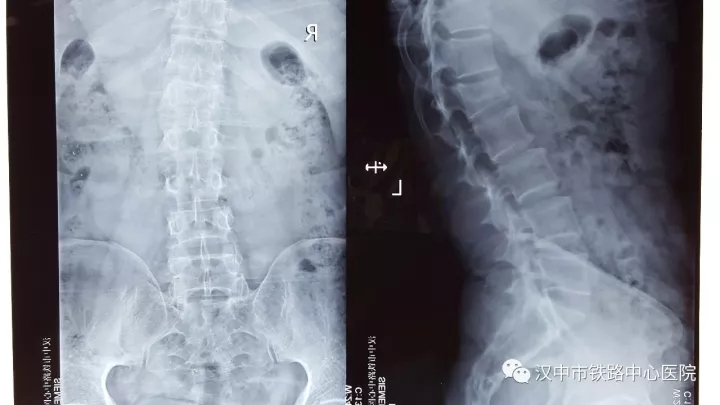

45岁的张先生是汉台区人,因从2米高处坠落臀部着地致腰背部疼痛、活动受限,诊断为腰1椎体压缩性骨折(II度)。10月19日,胡昭华博士主刀为其进行后路腰1椎体压缩性骨折经皮微创置钉内固定术,手术仅耗时两小时,术中出血仅20毫升。